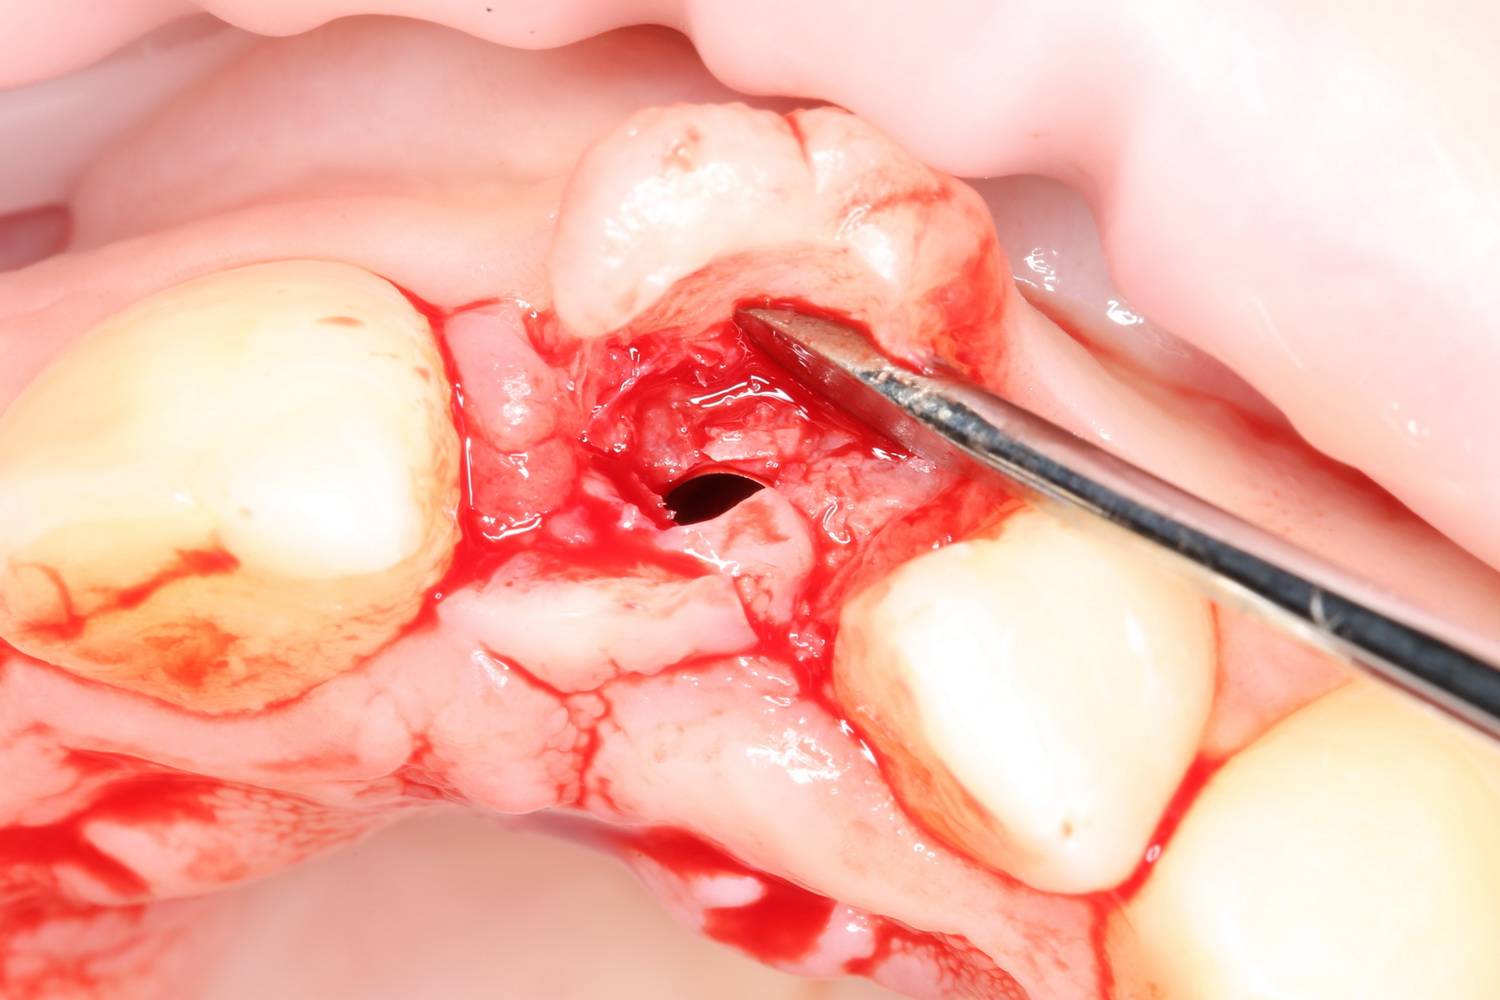

Делаем анестезию, разрез, скелетируем костную ткань:

На фотографиях хорошо видны оставшиеся после удаления объемы костной ткани. Давайте рассмотрим плюсы и минусы текущей клинической ситуации, применительно к нашему плану:

Фактически, альвеолярный гребень атрофировался по толщине примерно наполовину — это минус.

Зато с высотой все в порядке — это плюс

Немедленная нагрузка на имплантат невозможна — это минус. Почему? (см. Факторы…)

Достаточный объем кератинизированной десны, который даст нам возможность герметично запечатать послеоперационную рану — это, несомненно, тоже плюс. (вспомним факторы успеха остеопластической операции, часть III)

Ну и, оставшиеся объемы костной ткани позволят нам установить и правильно позиционировать имплантат — это главный плюс. А значит, мы обойдемся одной операцией вместо двух.